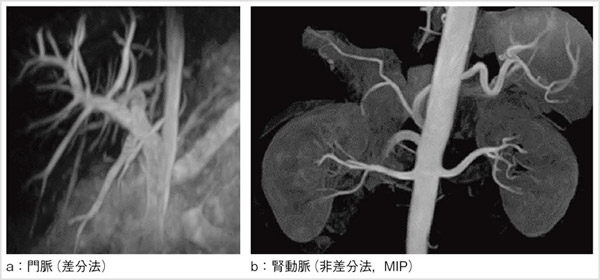

腹部のMRI MRI of the thoracic and the lumbar spine. A: sagittal T2の詳細情報

MRI of the thoracic and the lumbar spine. A: sagittal T2。116D52 | 卵巣腫瘍 国試 | テコプラ。腹部領域のMRI最新アプリケーション-技術解説 - 株式会社日立。Vertebral Compression Fracture - MRI Images - The Pain。「腹部のMRI」荒木 力定価: ¥ 13000#荒木力 #荒木_力 #本